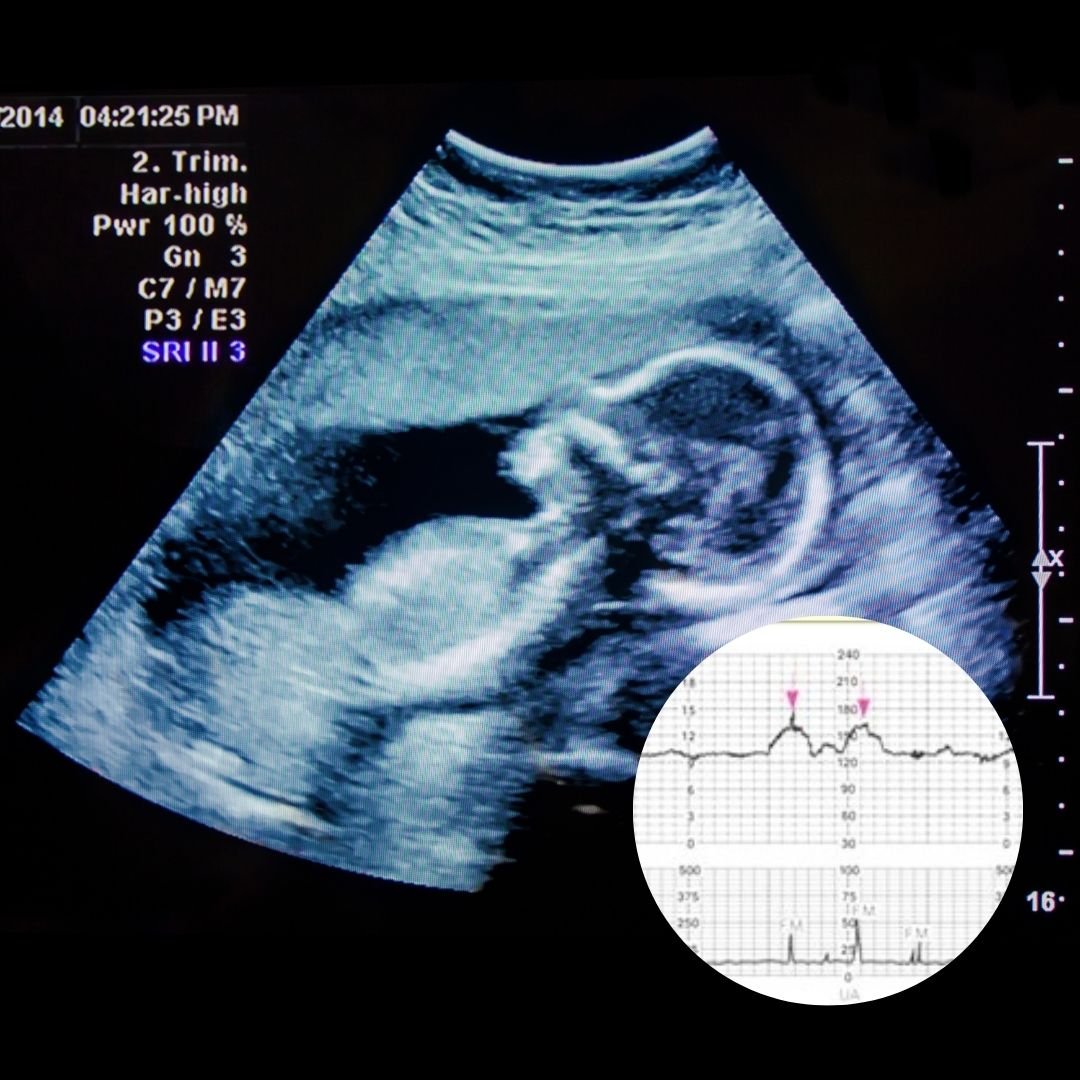

Our team of OB GYN consultants is committed to ensuring every visit is comfortable, informative and personalized with a focus on women’s health and wellness care.